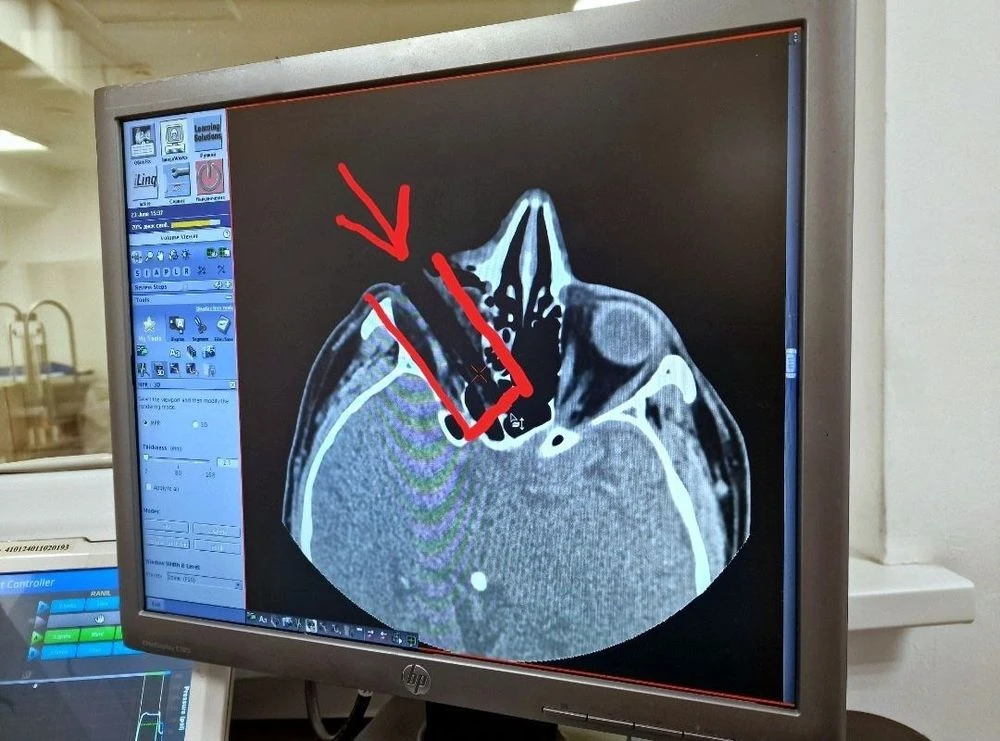

Врачи поставили шокирующий диагноз: проникающая рана глазницы с инородным телом и смещение глазного яблока и нулевое зрение. Глаз под веком не было видно, а глазное яблоко сместилось. Пациента экстренно увезли на операцию, где под микроскопом извлекли занозу и восстановили положение глазного яблока, удалив более 20 частиц коры и мелкого мусора. Благодаря быстрому вмешательству удалось избежать заражения, и глаз был спасён, а зрение частично сохранилось, сообщает пресс-служба больницы.